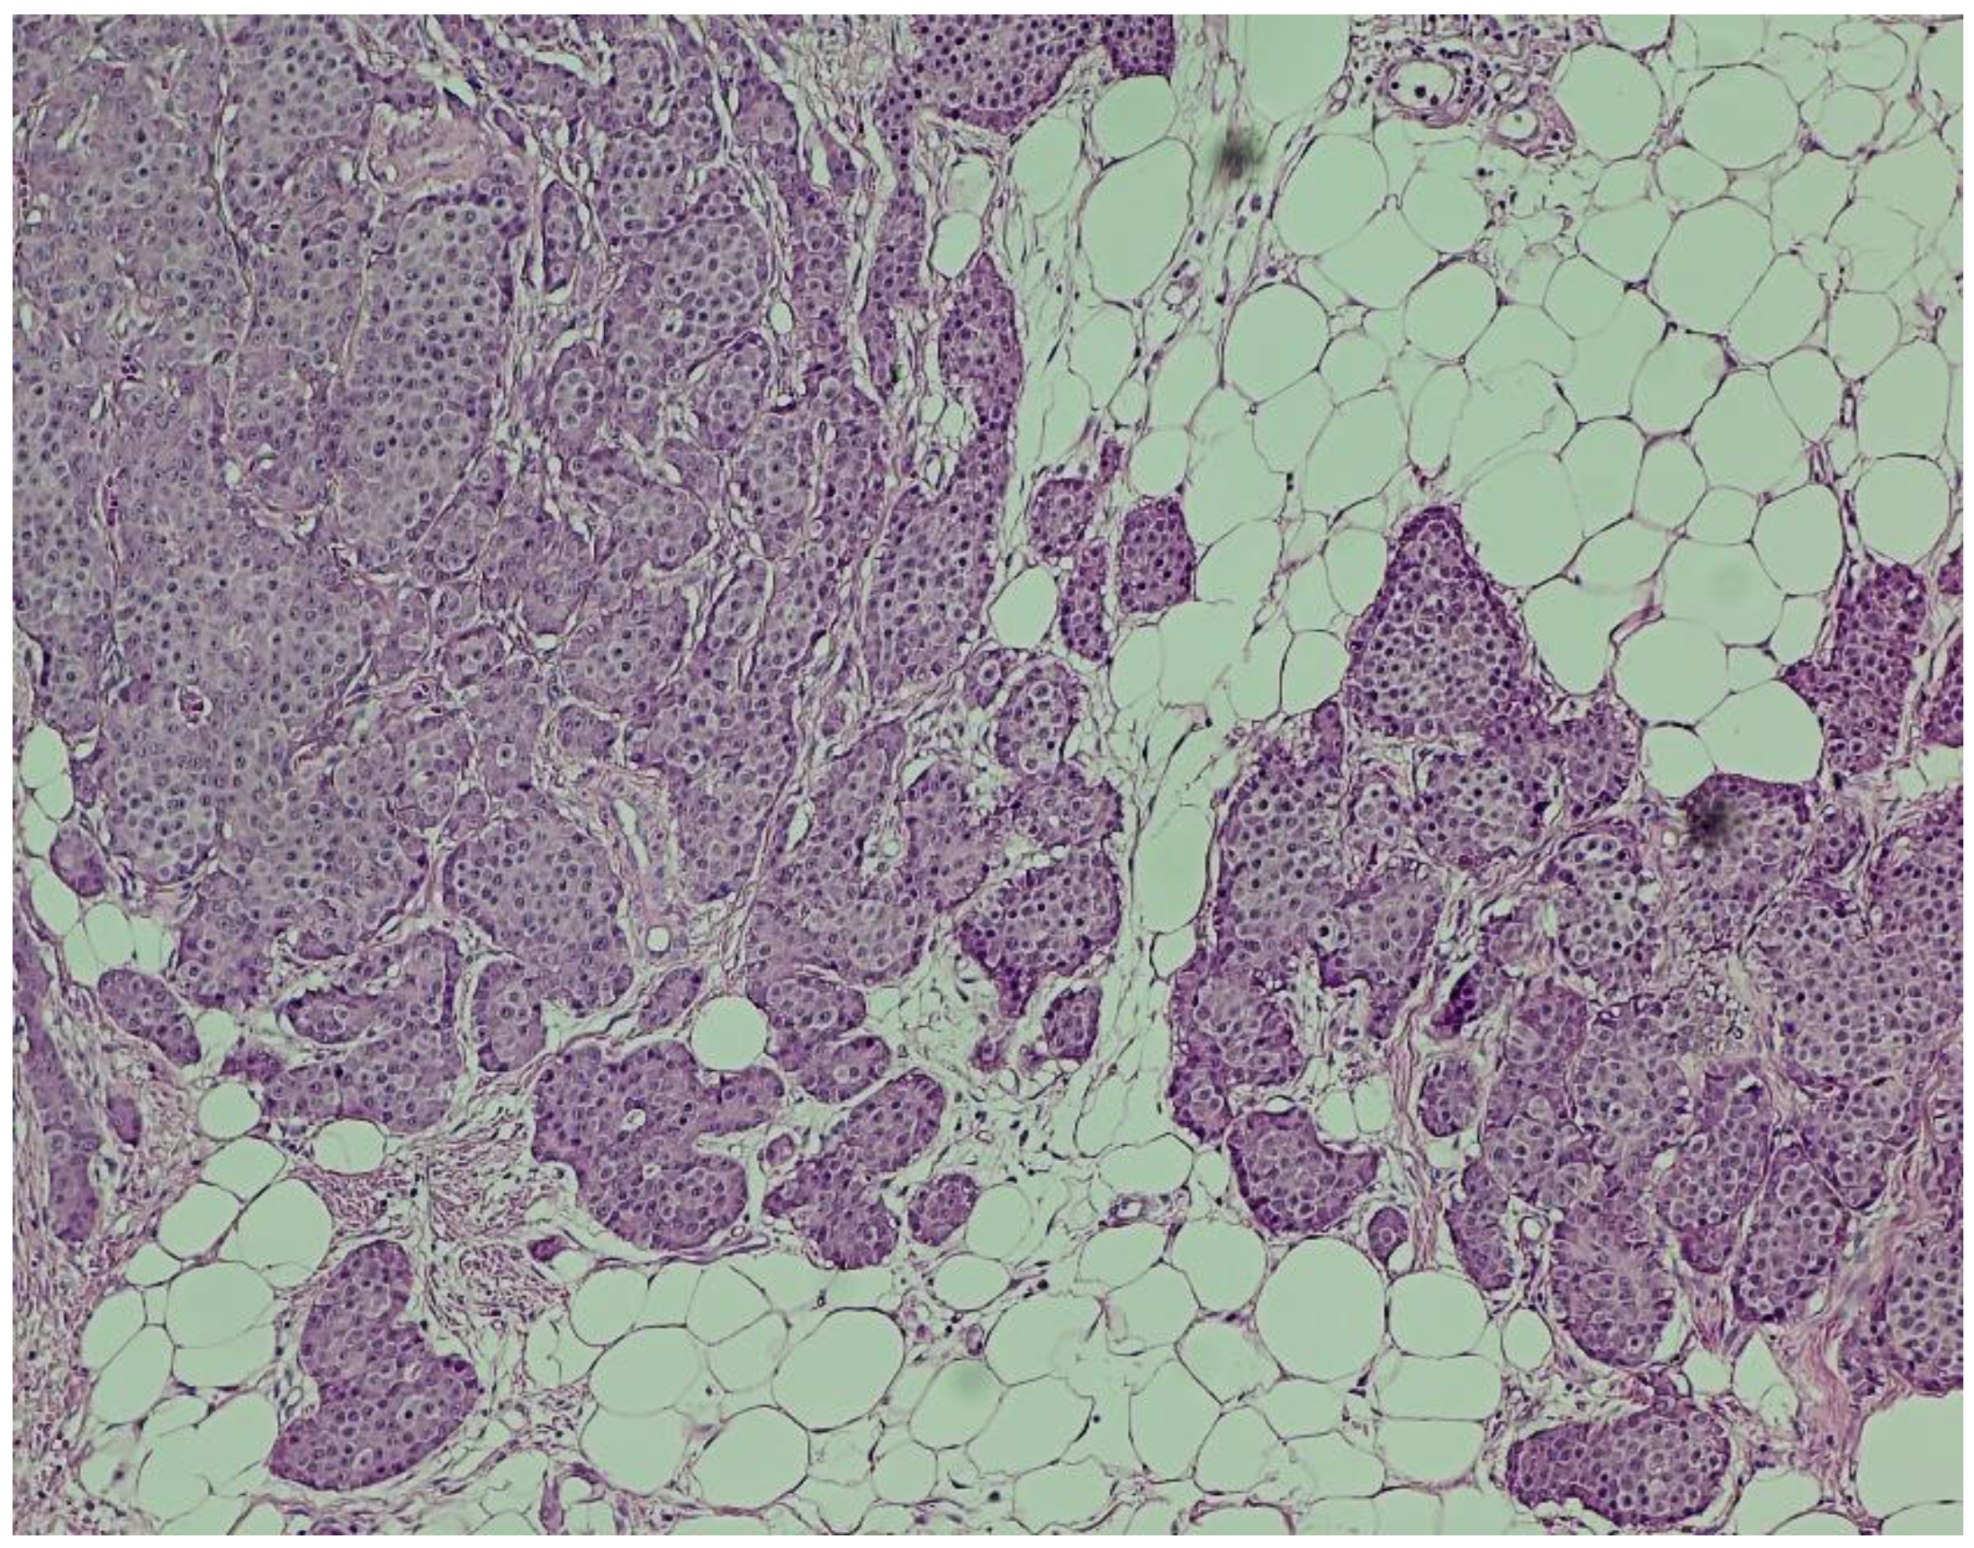

Histopathological Findings All surgical specimens were processed using standard histopathological protocols.

Hematoxylin and eosin (H&E) staining revealed a diffuse proliferation of tumor cells within adipose tissue, predominantly arranged in nested and insular patterns, with focal areas of trabecular architecture. The neoplastic cells were uniform in appearance, displaying round to oval nuclei, finely granular “salt-and-pepper” chromatin, and scant eosinophilic cytoplasm (Figure 4). Mitotic figures were rare (fewer than two per ten high-power fields), and no areas of tumor necrosis were identified—features consistent with a well-differentiated neuroendocrine tumor.

Immunohistochemistry (IHC) showed diffuse and strong positivity for chromogranin A and CD56, with focal weak staining for synaptophysin, supporting neuroendocrine differentiation (Figure 5, Figure 6, Figure 7 and Figure 8).

The Ki-67 proliferation index was estimated at approximately 3%, corresponding to a grade 2 (G2) neuroendocrine tumor according to WHO classification.

Figure 4. Hematoxylin and eosin (H&E) staining (×100). Nests of uniform neuroendocrine tumor cells exhibiting round nuclei, “salt and pepper” chromatin, and minimal cytological atypia, consistent with a well-differentiated morphology.